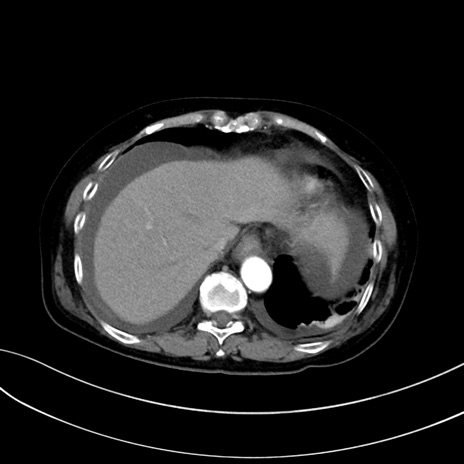

症例13 CT(横断像)1日半後